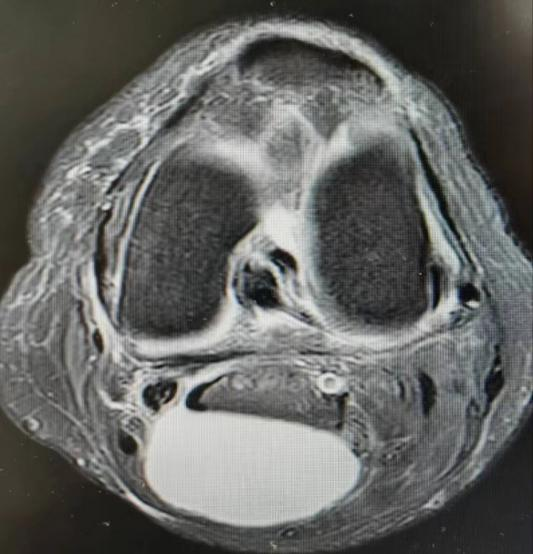

病例1,患者左膝关节疼痛不适半年,行经查体及MRI检查诊断为:左膝内侧半月板损伤、腘窝囊肿、骨性关节炎,给予行“左膝关节镜下内侧半月板、软骨修整成形及腘窝囊肿切除术”。

病例2,患者左膝关节疼痛不适2月,经查体及MRI检查诊断为:左膝内外侧半月板损伤、腘窝囊肿、骨性关节炎,考虑囊肿较小,且为单房囊肿,行“膝关节镜下半月板、软骨修整成形术”的同时,给予切除“活瓣”,行“腘窝囊肿减压术”。